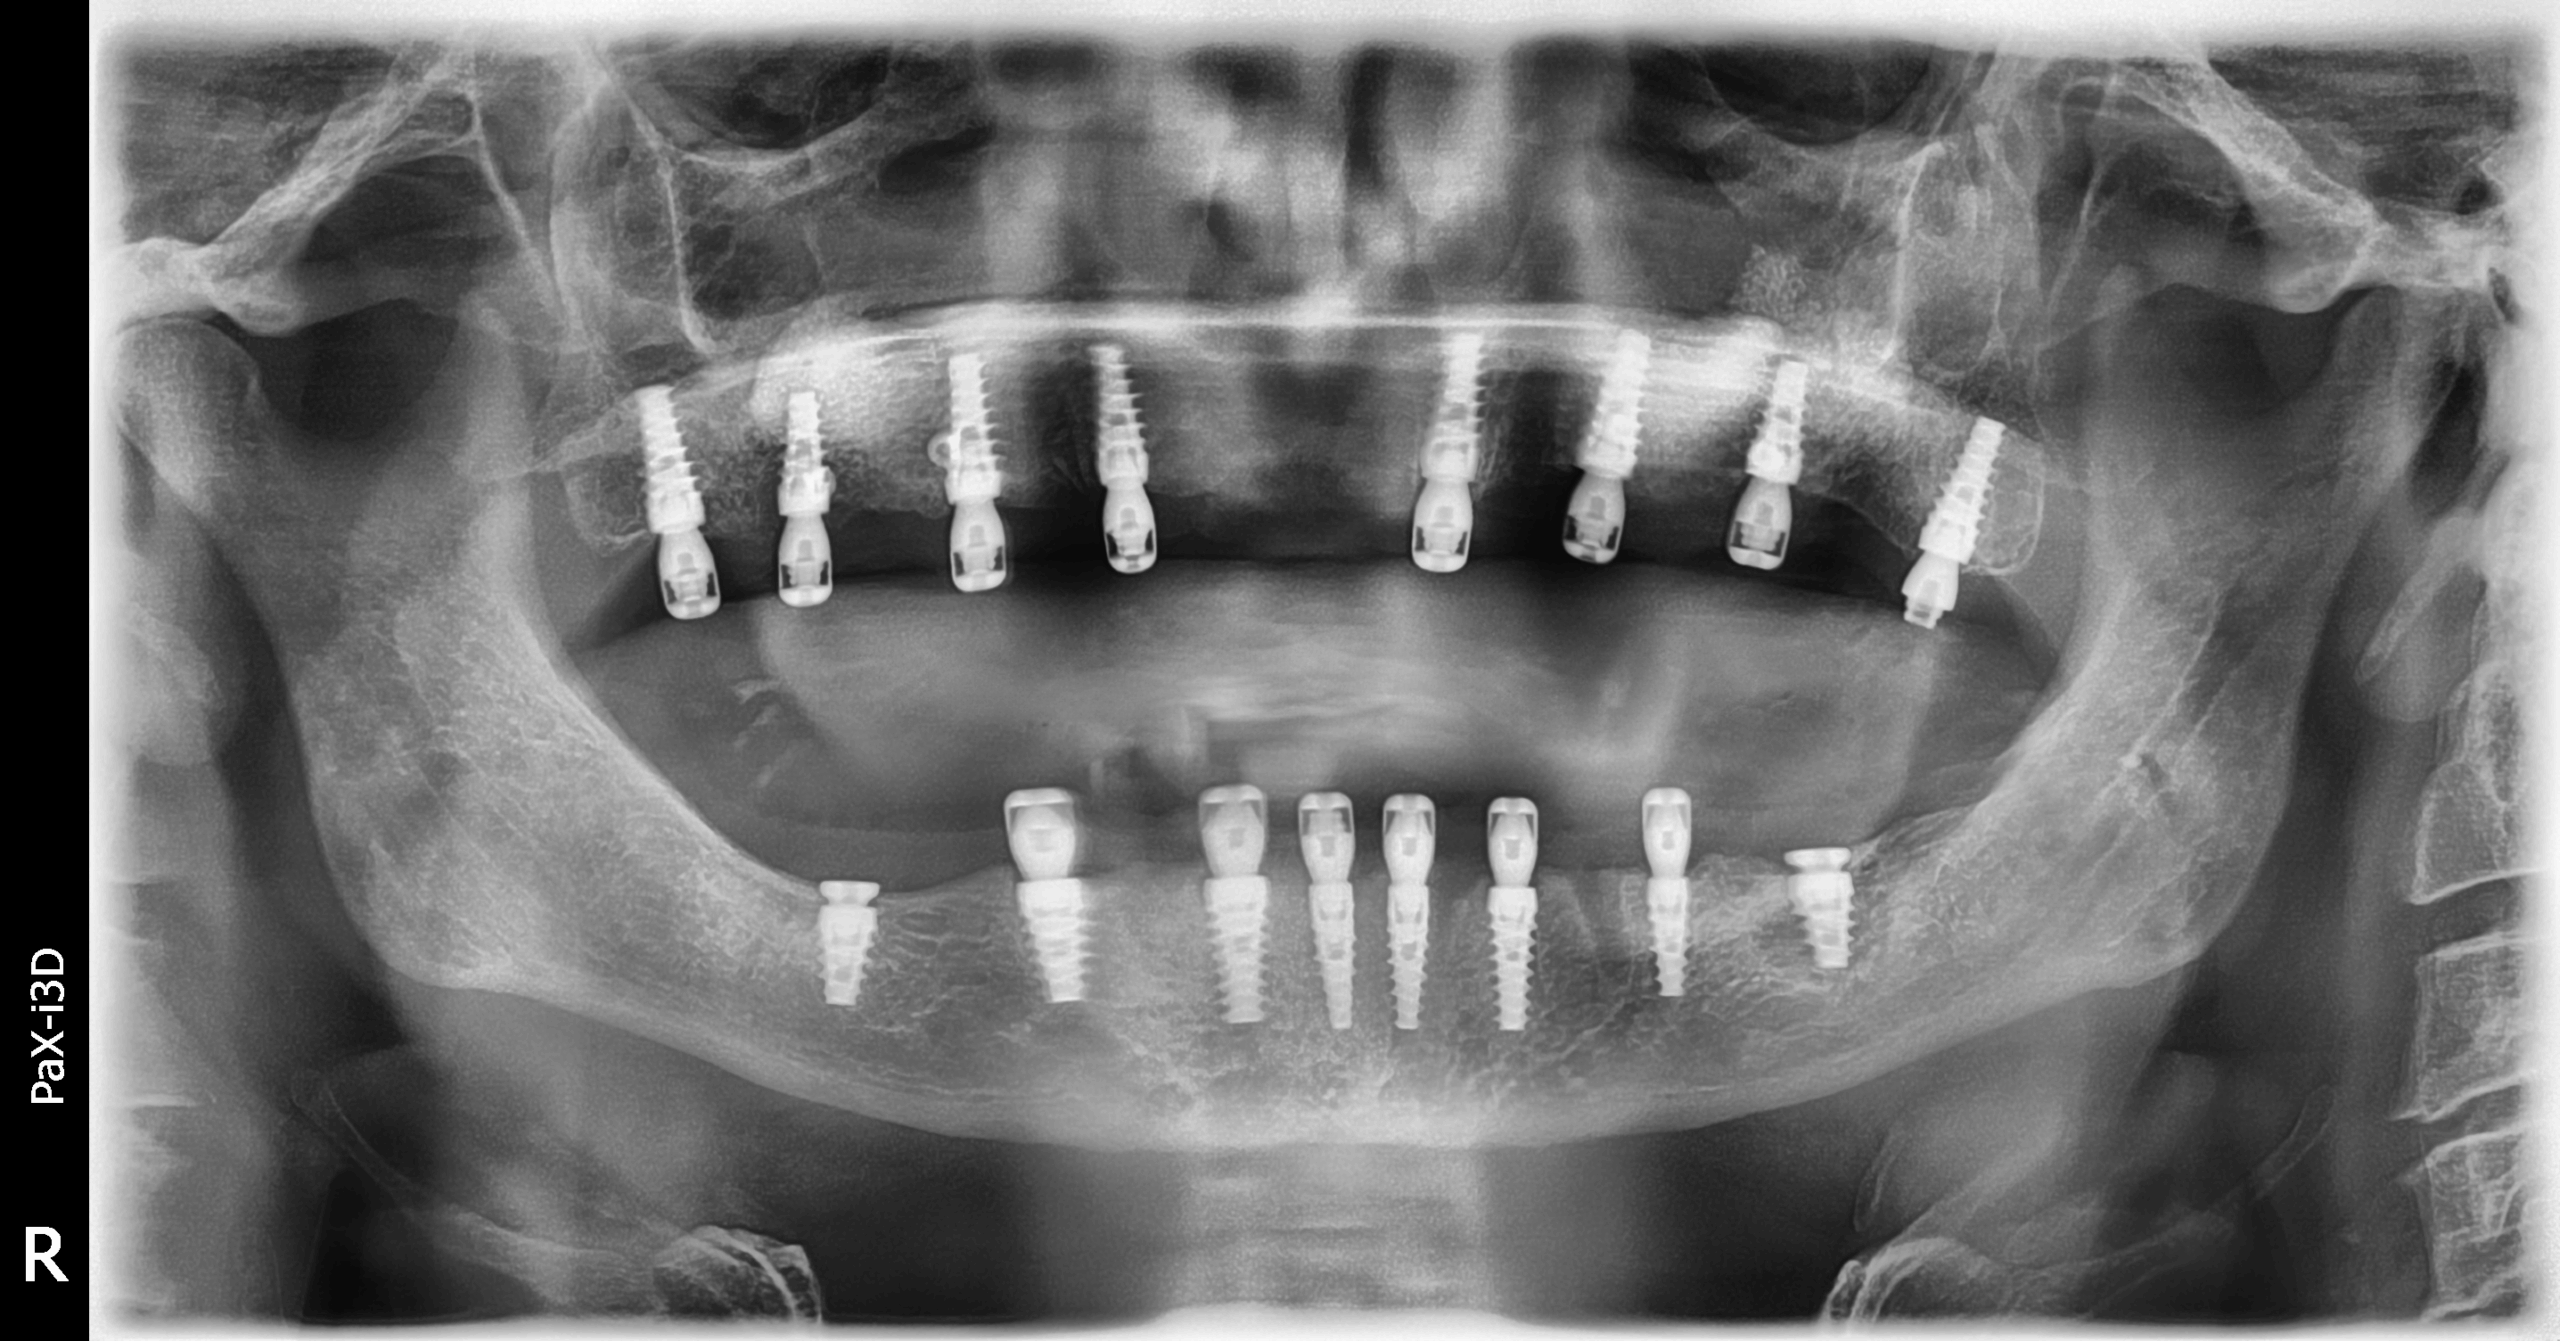

Implantes PCI

Secuencia de imágenes RX, antes y después de la inserción de implantes PCI en la parte superior e inferior de la boca.

Paciente varón de 75 años.

- Colocación de implantes Radhex PCI en la parte superior

- Colocación de implantes Radhex PCI en la parte inferior.